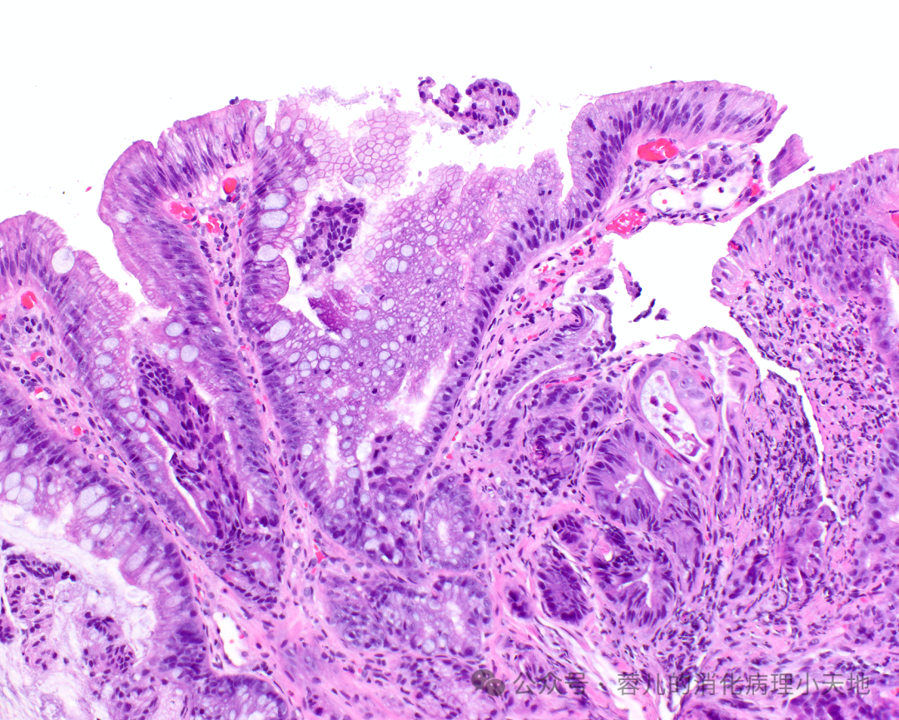

形成病变的胃异型增生(肠型腺瘤)具有肠型表型,表现为密集的腺体,由深染的肿瘤细胞排列而成,累及胃窦黏膜

病变细胞缺乏粘蛋白,并含有铅笔状假复层核,这些核保持与基底膜的关系